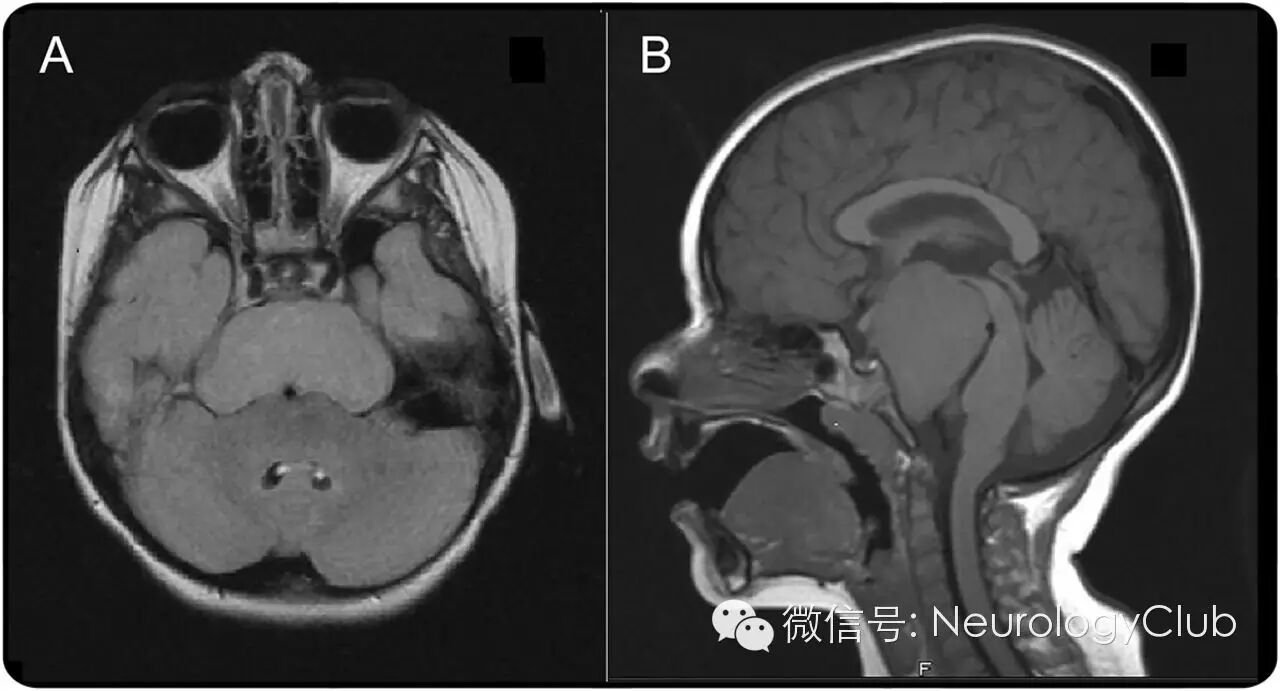

头颅MRI可见信号均匀的肿块(大小约为3.5×5×6cm)位于桥前池,起源于下丘脑。肿瘤前方靠近视交叉,后方压迫中脑和脑桥,无明显水肿。